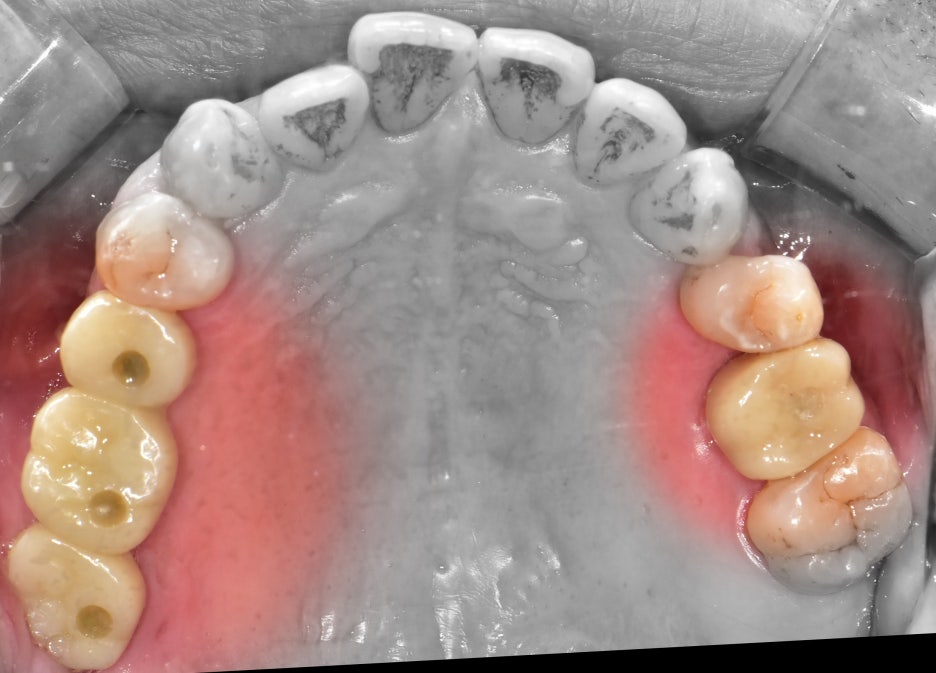

『선생님, 저 맛있게 밥 좀 먹는게 소원입니다.

다수 치아 결손 환자』

저를 찾아오셨던 이 분은, 이미 치아들이 많이 결손이 된 상태로 오셨었습니다.

한 쪽에는 뿌리만 남아있는 치아, 그리고 다른 곳에는 아예 치아들이 없는 상태입니다.

맞물리는 치아들은 앞니밖에 없는데 앞니로는 고기를 뜯거나, 질긴 음식을 드실 수 없죠.

즉, 교합 관계 불량에 따라서 올바른 저작 활동을 하실 수 없는 상태로 판단 되었었습니다.

사진에서 보실 수 있는 것 처럼 먼저 3개의 고정체를 심었습니다.

편측으로 먼저 지르코니아 크라운까지 다 올려드린 뒤에 남은 편측을 진행합니다.

시간이 또 대략 2개월 가량이 흘러서 이렇게 지르코니아 크라운까지 시적을 해드리면

반대편 또한 고정체 1개를 심어드리게 됩니다. 물론, 여기에도 상악동 거상술 은

진행했었습니다.

『최종 완성, 1년 소요』

양측으로 다 4개의 임플란트를 심었고, 여기에 상악동 거상술 및 뼈이식에 따라서

회복을 하는 기간을 포함하여 총 1년이 소요 되었습니다.